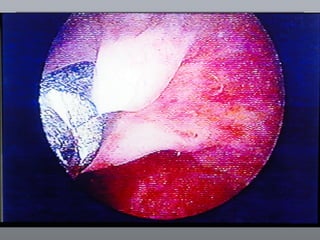

CÂNCER DE BEXIGA Estudos endoscópicos Biópsias randomizadas

Cistoscopia

CÂNCER DE BEXIGAEstudos endoscópicos Biópsias randomizadas